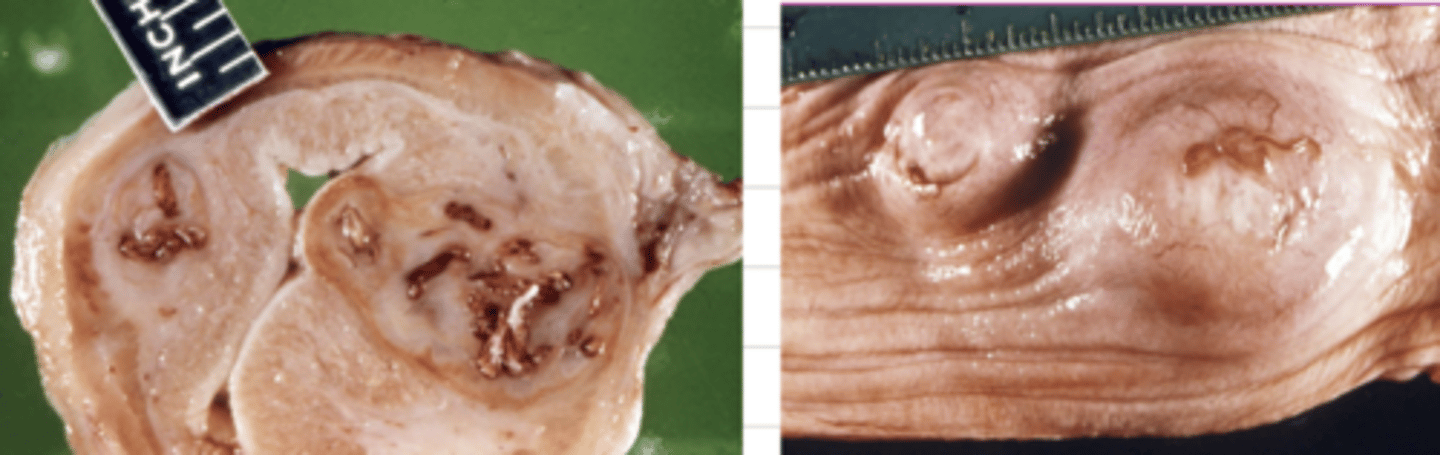

Spirocerca lupi

spirocercosis

what parasite has infected this esophagus? what is this disease?

what parasite makes these characteristic nodules in the esophagus of cats and dogs?